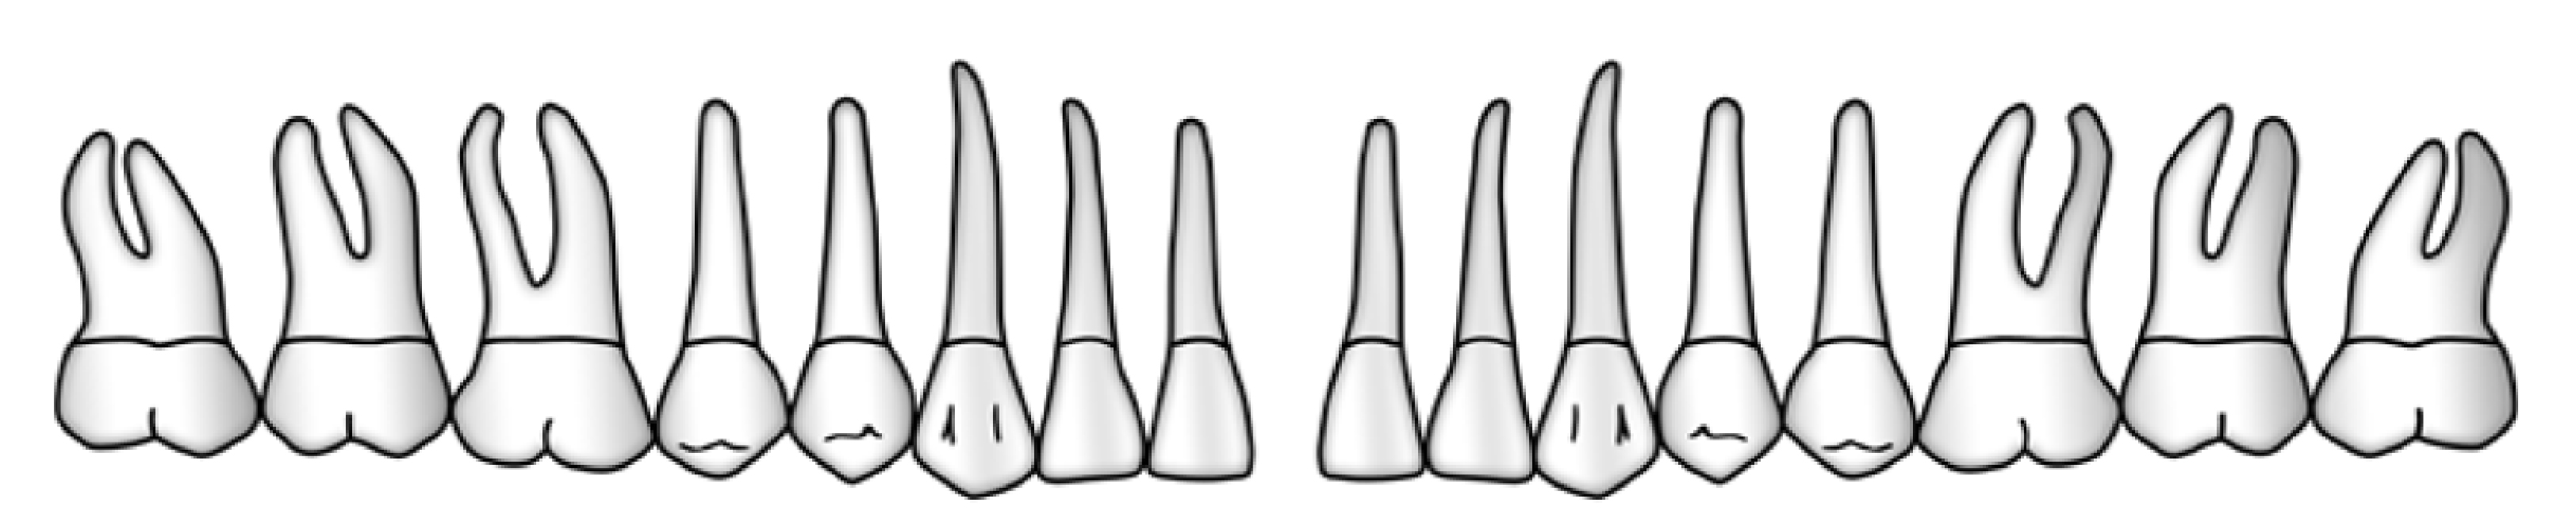

Sechs Messstellen pro Zahn oder Implantat

Entscheidend für die Aufzeichnung sämtlicher parodontalen oder periimplantären Messungen ist die Wahl der richtigen sechs Stellen um den Zahn oder um das Implantat. Hierfür wird der Zahn oder das Implantat von okklusal betrachtet in seinem Umfang in 6 Abschnitte eingeteilt. Für jeden dieser Abschnitte wird die Stelle mit dem höchsten Sondierungswert ermittelt und ausgemessen.

2. Furkationsbefall

Die Furkationen der Molaren sowie der ersten Praemolaren im Oberkiefer werden mit einer Furkationssonde untersucht. Die horizontale Komponente der gesamten Eindringtiefe wird nach folgenden Kriterien in die Grade 0 - 3 eingeteilt (Hamp et al., 1975).

Grad 0 Furkationseingang nicht sondierbar

Grad 1 Furkation sondierbar, horizontaler Sondierungswert ≤3mm

Grad 2 Furkation sondierbar, horizontaler Sondierungswert >3mm

Grad 3 Furkation durchgehend offen